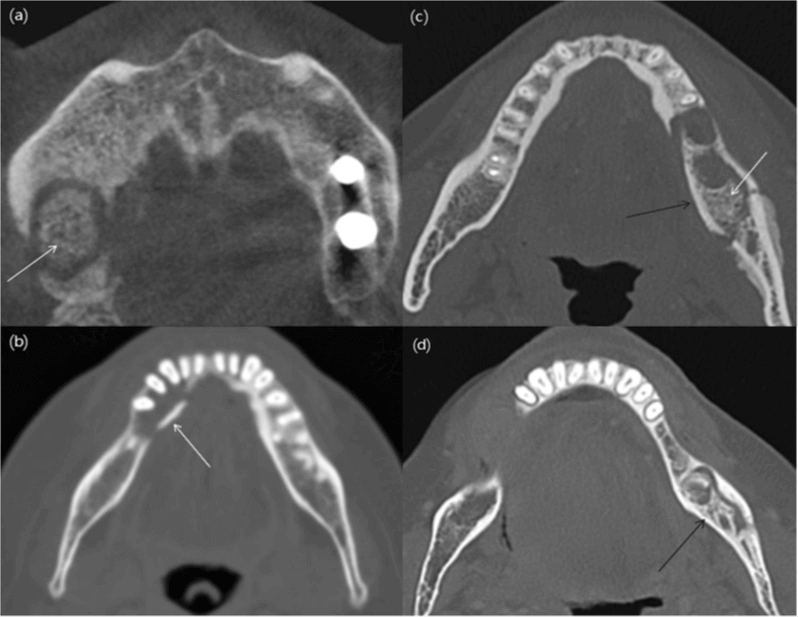

En las radiografías panorámicas, se pueden observar diferentes patrones de las lesiones y se clasifican como osteolítico, esclerótico o mixto. Se evaluó la presencia de secuestros, formación de hueso perióstico nuevo, afectación del hueso cortical y afectación del canal mandibular. Se analizaron los cambios en los tejidos duros en las imágenes de tomografía computarizada. Estos cambios en los tejidos duros incluían la presencia de defectos trabeculares y corticales, esclerosis, secuestros y formación de hueso nuevo periótico. Los secuestros se clasificaron como trabeculares, corticales, mixtos trabeculares y corticales o incompletos. Además, el patrón de hueso nuevo perióstico se clasificó como laminar continuo, laminar interrumpido y sólido. Las imágenes de tomografía computarizada se evaluaron para detectar cambios en los tejidos blandos, como inflamación, celulitis, tejido de granulación, sinusitis o mucositis, abscesos, miositis y fístulas.